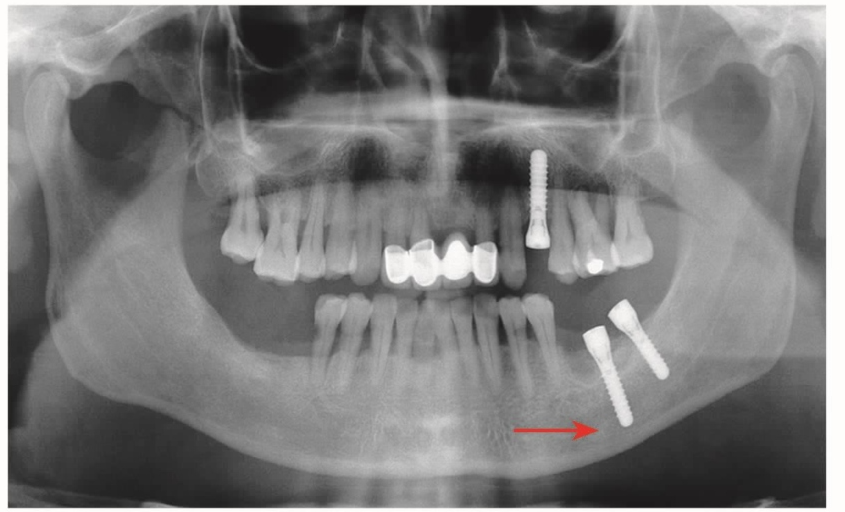

6 种植体折断

种植体的发展历程也是循序渐进的,20世纪90年代可以看见一段式的叶状或者细长的螺钉状种植体,现在已经淘汰。那类种植体可以看见有折断的发生,而现在的种植体一般不容易发生折断。种植体过细或者应力过大都可能造成种植体折断(图12)。

图12 全景片局部A.种植体折断(箭头);B.第二次重新植入直径较粗的种植体